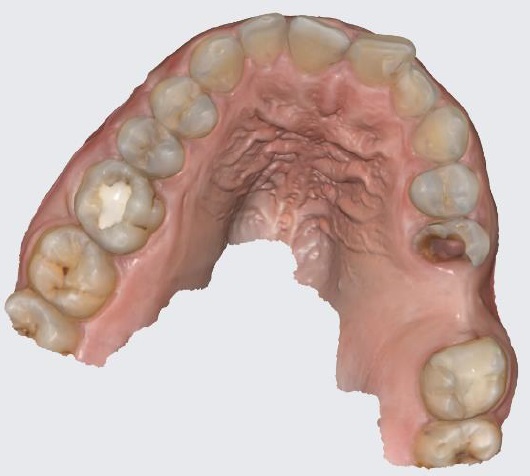

Материалы и методы исследования. На этапе подготовки к хирургическому вмешательству пациенту выполняется конусно-лучевая компьютерная томография (КЛКТ) челюстей и интраоральное сканирование полости рта (рис. 1). Эти исследования позволяют собрать ключевые данные для точного планирования лечения.

Рис. 1. Проведение сканирования полости рта пациента для удаления 25 зуба

2. Fig. 1. Scanning the patient's mouth for extraction of tooth 25

Download (45KB)